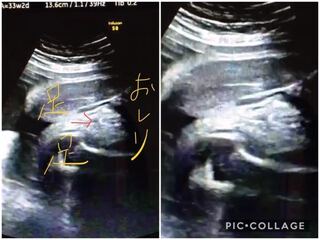

こちらはコーヒー豆や葉っぱのような割れ目(シンボル)のようなものが見えるのが分かりやすい写真です。 妊娠25週目の女の子のエコー写真 こちらは25周目の女の子のエコー写真。 右側がおしり、左側が足です。フレーバーコーヒーとは、北欧を中心としたヨーロッパでコーヒーに シナモンやアイリッシュリキュール等の香り付けをして飲まれていたのが始まりと言われていますが、 1980年頃、米国でコーヒー豆に香りをつけて焙煎する方法が開発され、 コーヒーの新しい楽しみ方でポピュラーな飲み物超音波エコー ベビーナブも超音波で確認をするのですが、超音波エコーとは一般的に 「実際に性器がどう映るか? 」 で判定するものです。 男児は突起物が、女児は木の葉の形、コーヒー豆の形に見えると言われています。

妊婦健診 33w0d 割れ目くっきり でも性別確定してもらえず ノd Miyaco Log